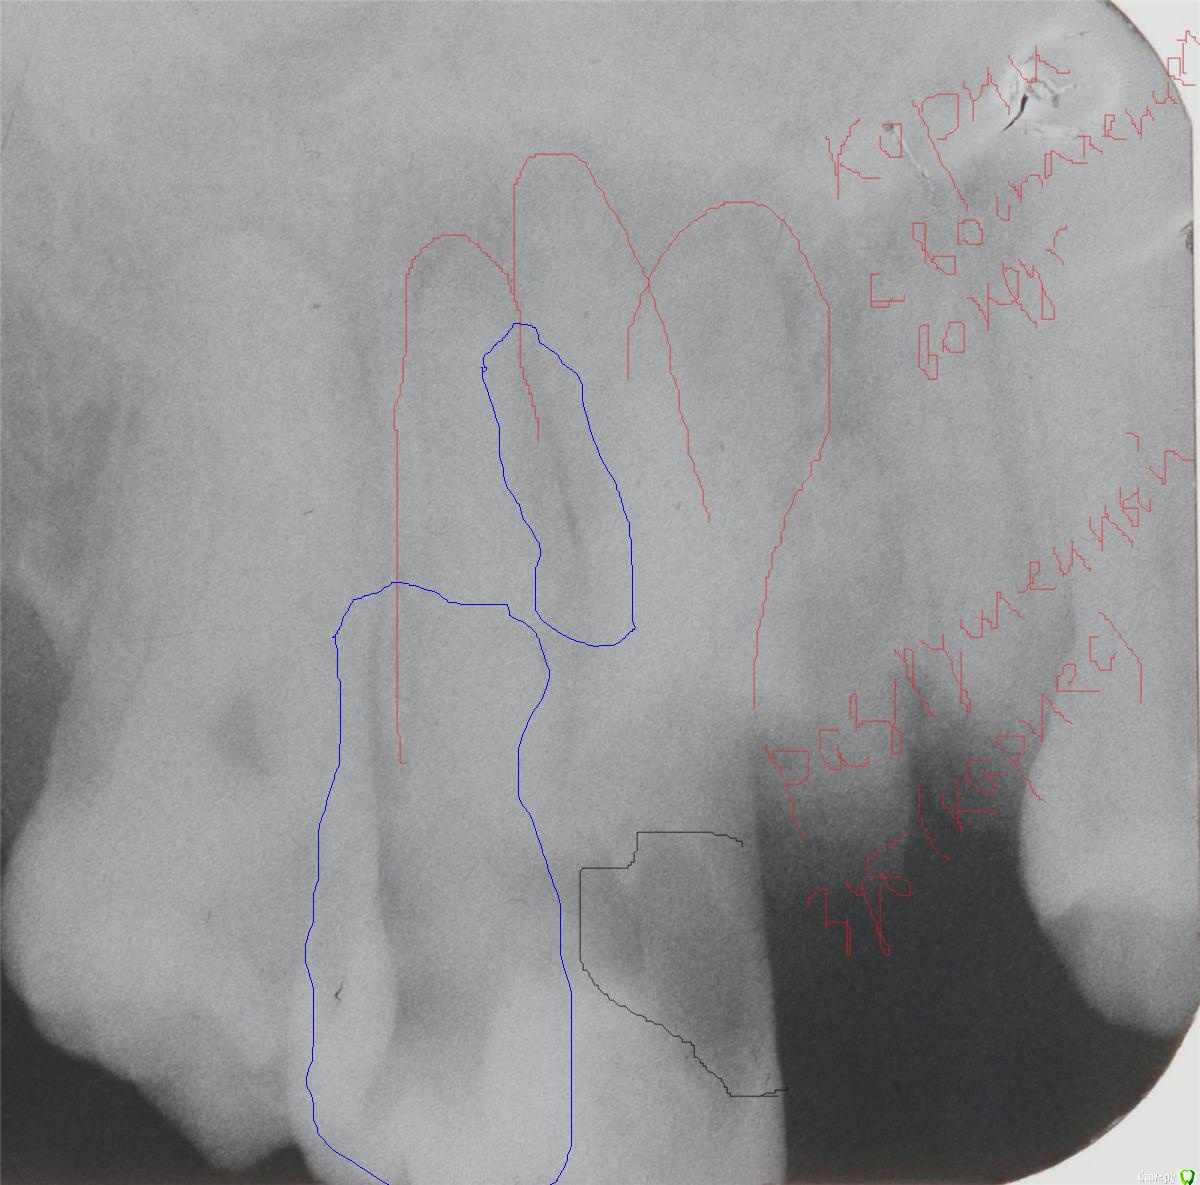

stomt Опубликовано 16 февраля, 2016 Автор Поделиться Опубликовано 16 февраля, 2016 Вот эта темная область обведенная синим в надкоренной зубе меня интересовала изначала, ну и меньшая часть обведена синим между корнями тоже непонятно что значит. Ссылка на комментарий

red_butler Опубликовано 16 февраля, 2016 Поделиться Опубликовано 16 февраля, 2016 Это наложение различных анатомических структур, а именно корней зубов друг на друга.Еще вопросы, или уже к лечению перейдете? Ссылка на комментарий

stomt Опубликовано 16 февраля, 2016 Автор Поделиться Опубликовано 16 февраля, 2016 Снова таки - мой вопрос (вопрос темы) был касательно темной области вне кореня, где обведено синим, а не меньшей части обведенным синим - это уже попутный вопрос, хотя там кажется расхождение корней, естественное или уже приоретенное, а не накладывание (это мое мнение как не специалиста). Как там может быть наложение корней - там ведь нету двох рядов... Ссылка на комментарий